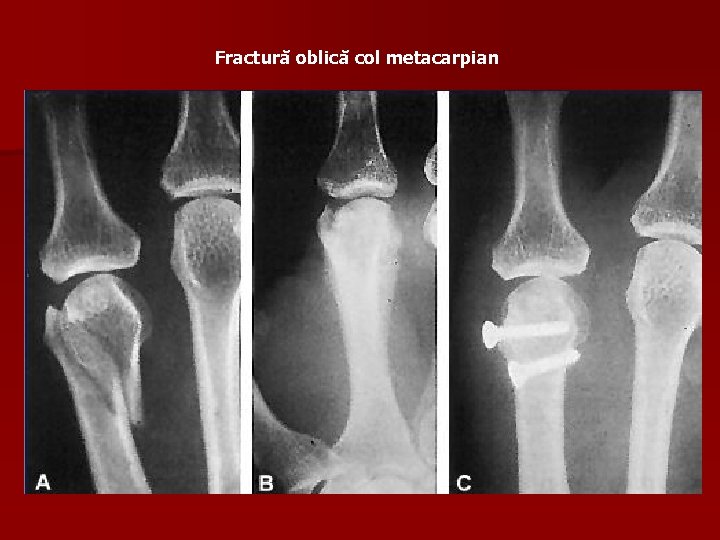

Fractură oblică col metacarpian